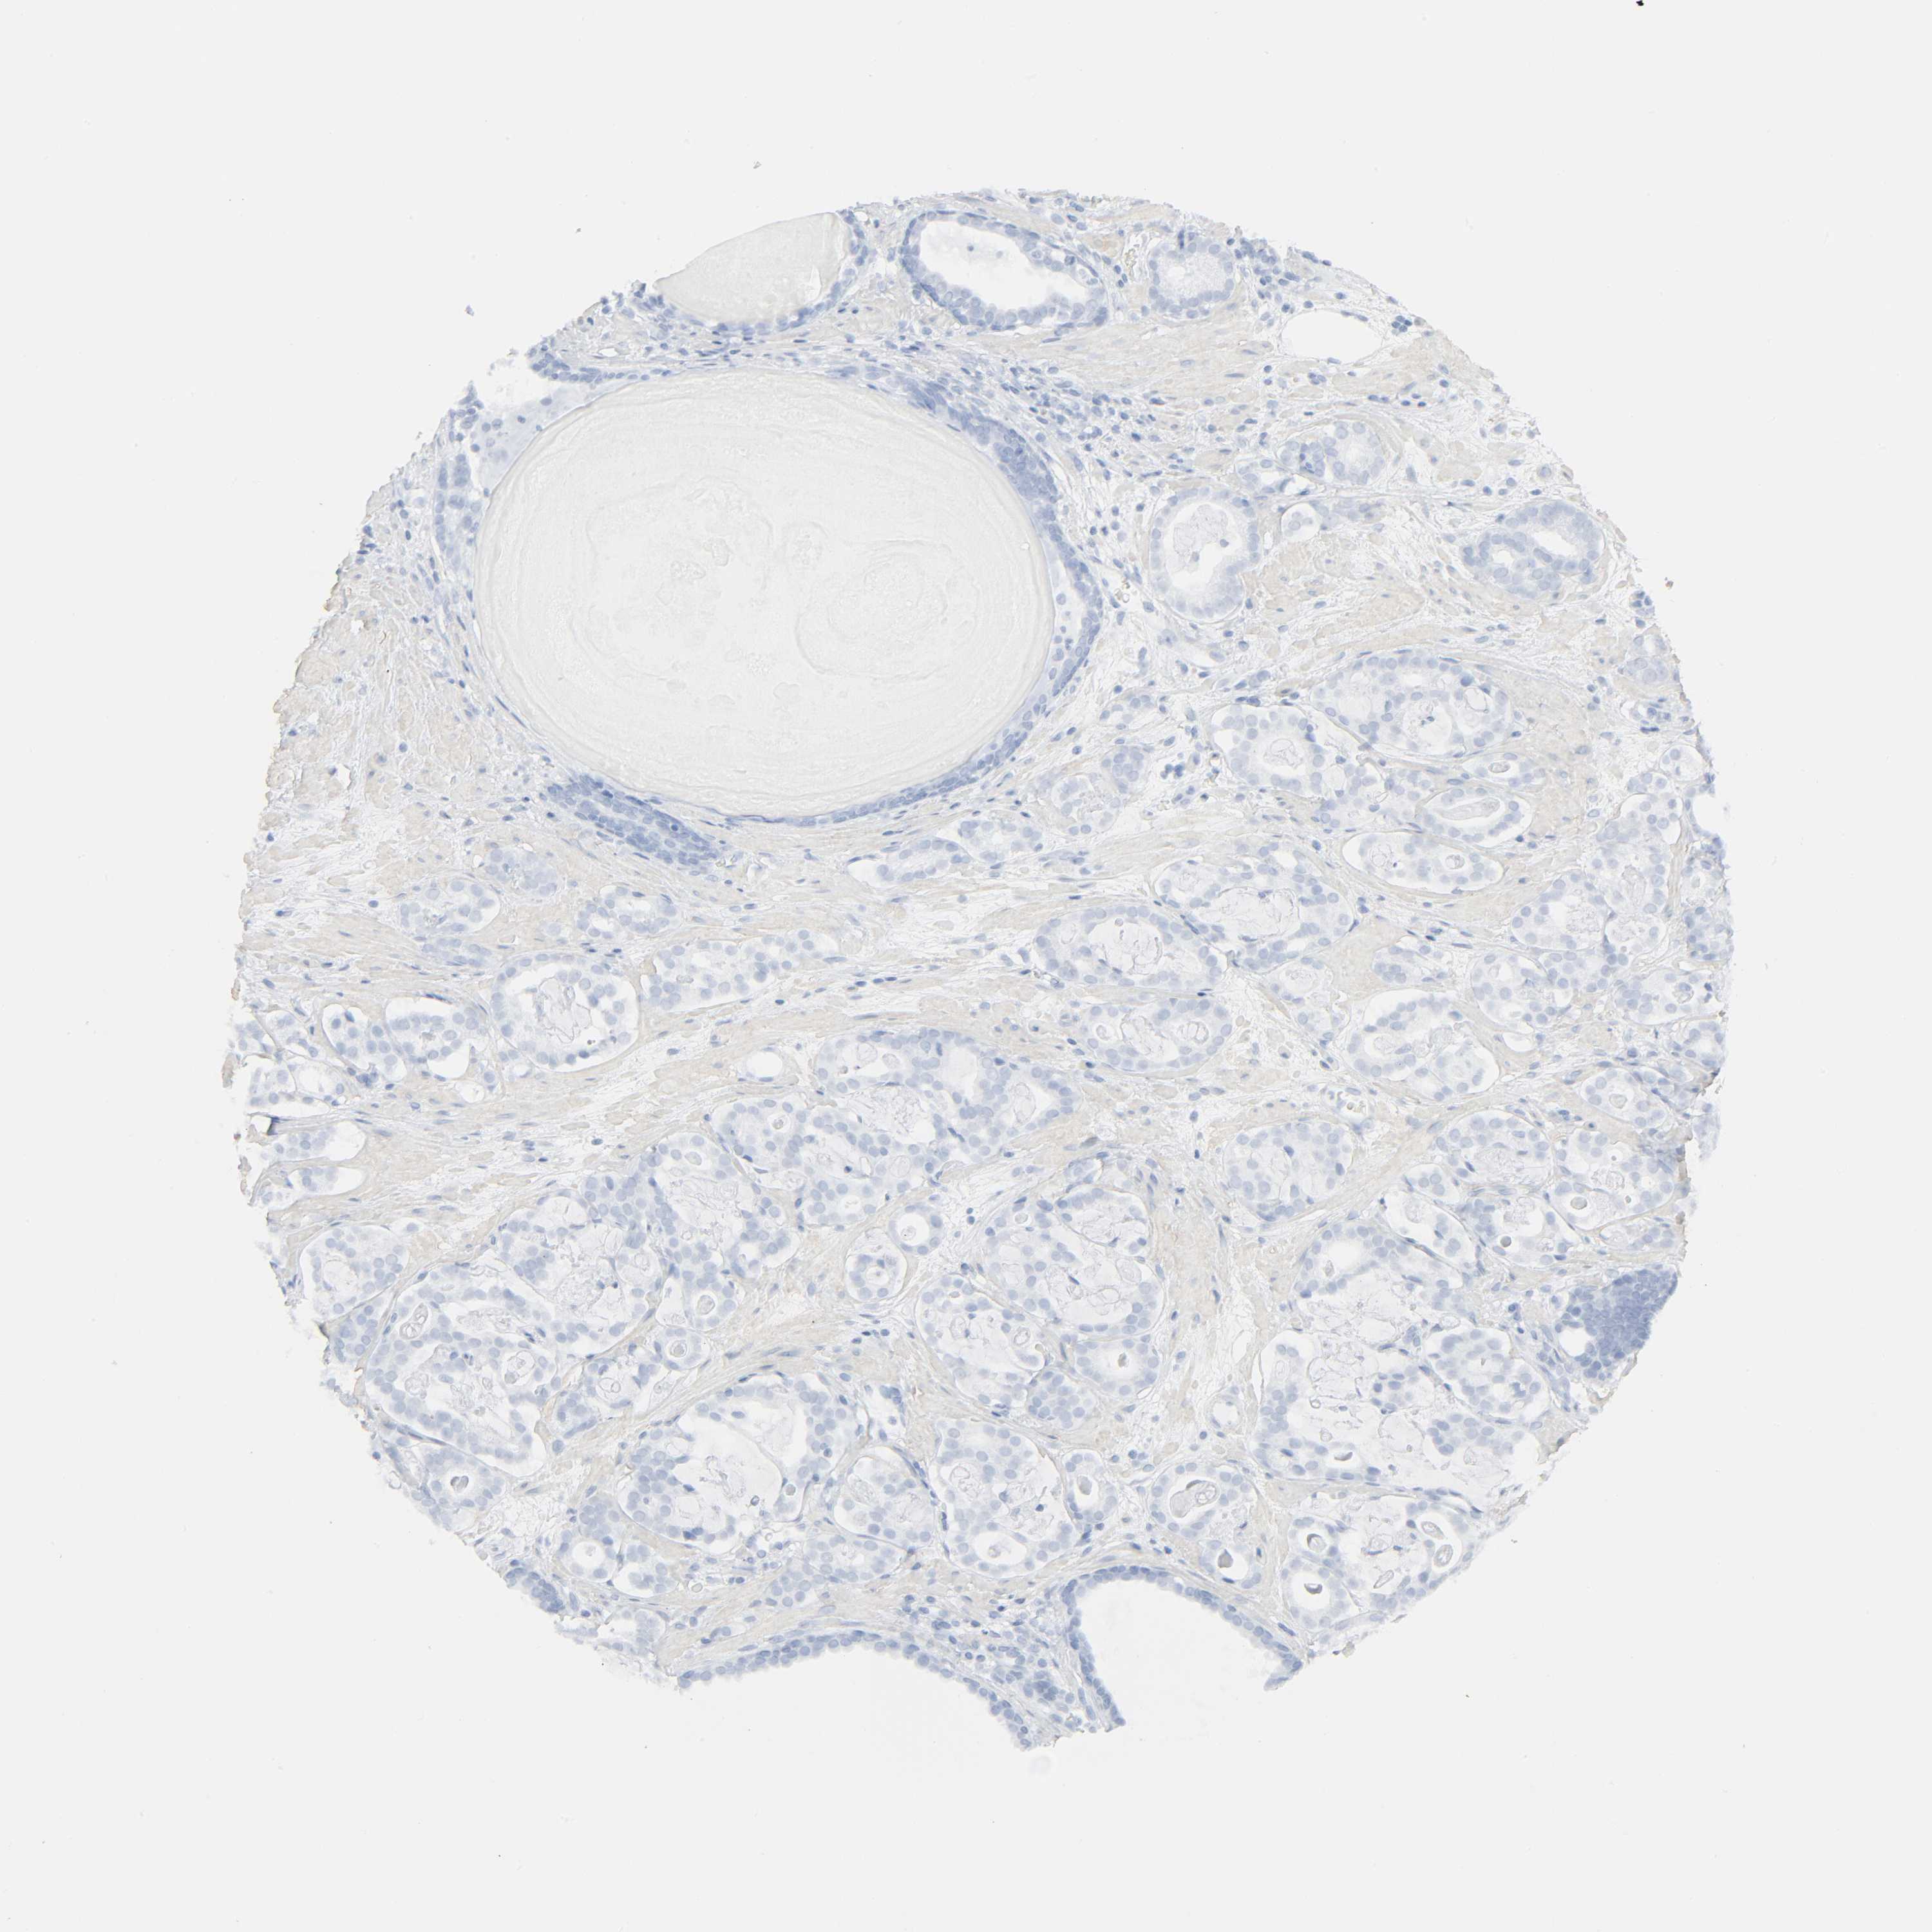

PROSTATE CANCER - Protein expressioni

A mouse-over function shows sample information and annotation data. Click on an image to view it in a full screen mode. Samples can be filtered based on level of antibody staining by selecting one or several of the following categories: high, medium, low and not detected. The assay and annotation is described here.

Antibody stainingi

Antibody staining in the annotated cell types in the current human tissue is reported as not detected, low, medium, or high, based on conventional immunohistochemistry profiling in selected tissues. This score is based on the combination of the staining intensity and fraction of stained cells.

Each image is clickable and will lead to virtual microscopy that enables deeper exploration of all samples and also displays staining intensity scores, fraction scores and subcellular localization as well as patient and tissue information for each sample.

Antibody HPA001499

Adenocarcinoma, Medium grade

Adenocarcinoma, High grade

Adenocarcinoma, Low grade